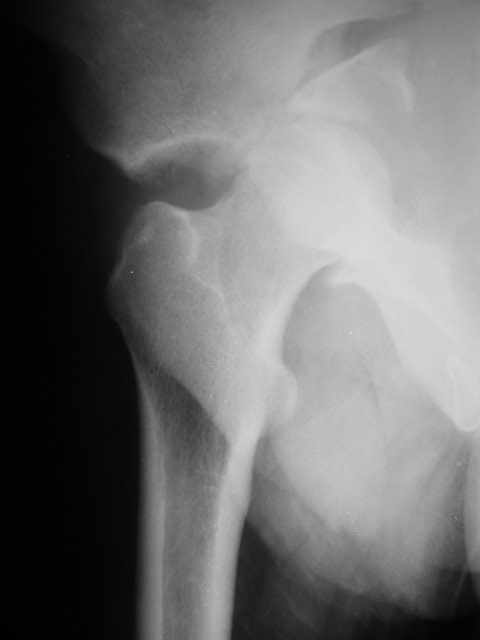

Подвздошная

P1010002.JPG

Алексей 23 Сентябрь 2004, 13:58

Вот что получилось (снимок операционный, качество не очень). Первый доступ был подвздошно-бедренный из которого разделили почти весь поперечный перелом, затем из задннего вправили вивих, выделили задний край и зафиксировали винтом.